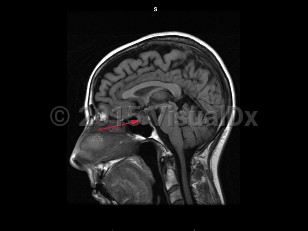

Craniopharyngioma

A craniopharyngioma is a brain tumor arising from pituitary embryonic tissue. It is typically suprasellar and has solid and cystic components. Age of onset can occur in childhood (about age 5-15) or adulthood (about age 50-70). There are adamantinomatous, papillary, and mixed types. Adamantinomatous tumors are more common in children and papillary tumors are more common in adults. A Rathke cleft cyst may develop from Rathke pouch if the pouch does not close normally.

Craniopharyngiomas are usually slow growing, and symptoms arise from compression of surrounding structures or increased intracranial pressure. Presenting symptoms include visual loss (most commonly superior temporal quadrantanopsia), headache, hormonal imbalances leading to delayed puberty in children, amenorrhea, hypersomnia, diabetes insipidus, and/or decreased libido. These tumors are usually benign with a good prognosis, but often recur when resection is incomplete.